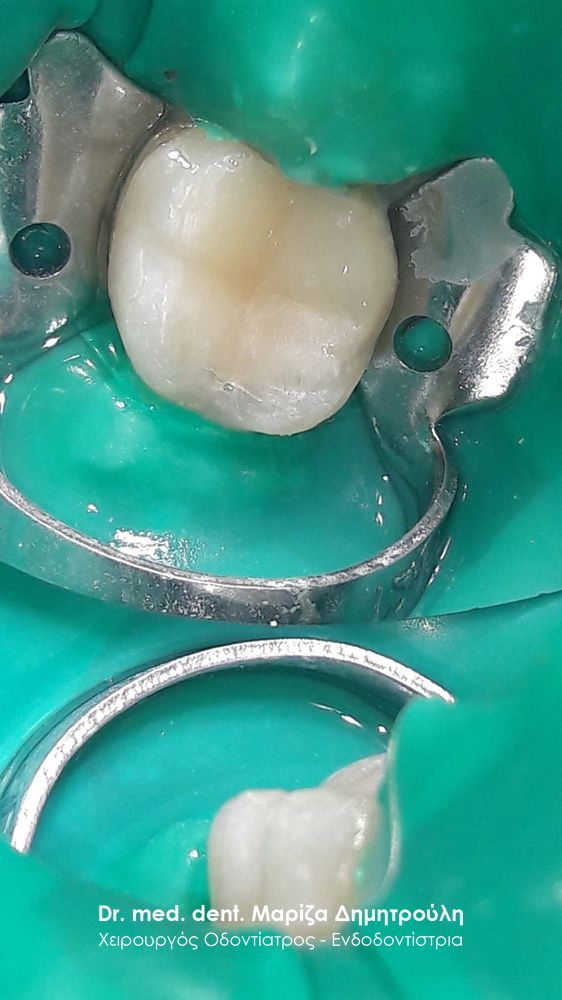

Περιστατικό – Αντικατάσταση σφραγισμάτων δοντιών

Ο ασθενής επιθυμούσε την αντικατάσταση των μαύρων σφραγισμάτων αμαλγάματος στον πρώτο δεξιό γομφίο και στο δεύτερο γομφίο με λευκά σφραγίσματα σύνθετης ρητίνης. Η θεραπεία πραγματοποιήθηκε με τη χρήση ελαστικού απομονωτήρα, όπως ορίζουν τα παγκόσμια πρωτόκολλα οδοντιατρικής για την αφαίρεση των μαύρων σφραγισμάτων. Όταν οι οδοντίατροι χρησιμοποιούν απομονωτήτρα κατά την αφαίρεση σφραγισμάτων αμαλγάματος, τότε ο ασθενής εισπνέει ελάχιστα και δεν καταπίνει τον υδράργυρο, που απελευθερώνεται κατά τη διαδικασία αυτή.

ΠΡΙΝ

META